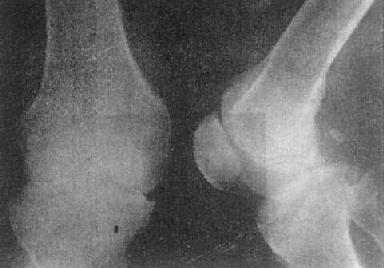

(三)关节退行性变 关节退行性变(degeneration lf joint)早期改变开始于软骨,为缓慢发生软骨变性、坏死和溶解,骨板被吸收并逐渐为纤维组织或纤维软骨所代替,广泛软骨坏死可引起关节间隙狭窄。继而造成骨性关节面骨质增生硬化,并于骨缘形成骨赘。关节囊肥厚、韧带骨化。

关节退行性变的早期X线表现主要是骨性关节面模糊、中断、消失。中晚期表现为关节间隙狭窄、软骨下骨质囊变和骨性关节面边缘骨赘形成,不发生明显骨质破坏,一般无骨质疏松。

这种变化多见于老年,以承受体重的脊柱和髋、膝关节为明显(图2-1-15、16),是组织衰退的表现。此外,也常见于运动员和搬运工人,由于慢性创伤和长期承重所致。不少职业病地方病可引起继发性关节退行性变。

关节退行性变-膝关节退行性骨关节病

图2-1-16 关节退行性变-膝关节退行性骨关节病

膝关节的关节间隙变窄,边角锐利,有骨赘形成,关节面平而致密